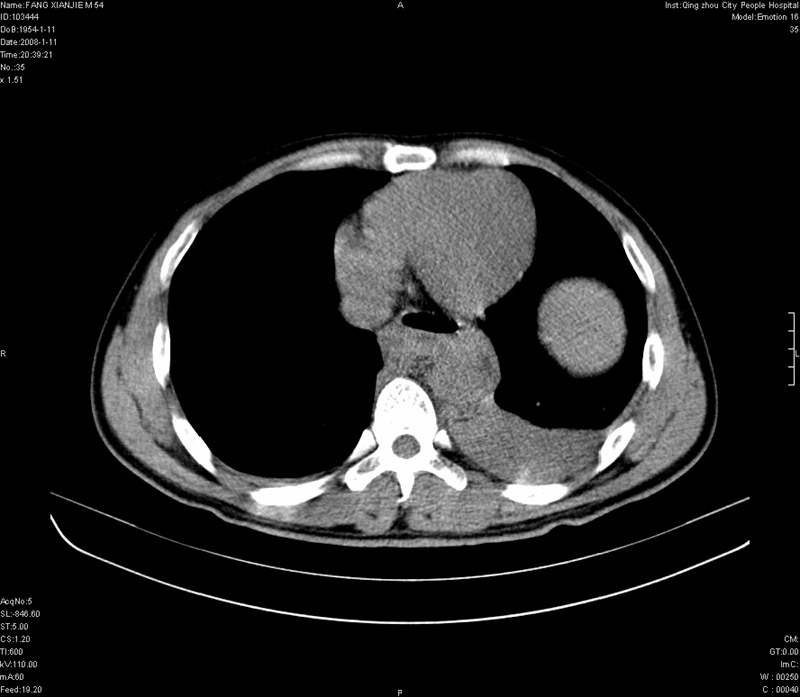

男性,40岁。胸部被车压伤伴胸痛1小时来院就诊。检查:一般情况尚可,血压110/80,胸部及上腹部压痛。结果在三天后公布。骨窗在横断位、冠矢状显示肋骨、胸椎、和胸骨未见骨折征象。

ct11308:胸部外伤1小时(证实病例) (2008-1-13 16:2)结果如下:病人入院后两小时后症状加重,8小时后在征得病人家属同意做了ct增强扫描。如下图。最终临床诊断:外伤性胸主动脉破裂并纵隔内血肿。由于有运动性伪影,胸骨在矢状面重建的图像似有骨折征,这是一种假象,我们称之为“假骨折”,这在多层ct重建中经常性遇到,必要时要结合横断图像鉴别之。现在,病人的一般情况较差,是否要手术家属尚有争议,如果手术修补,难度较大,需要专门预定制作固定支架。

当然,对于该病例,其它非重要的诊断还有:右侧少量气胸;左侧胸腔积液;左侧轻度肺挫裂伤。对于纵隔内血肿,我们曾经遇到过多例,也有怀疑主动脉的破裂,但是,均未得到具体出血部位的明确诊断。